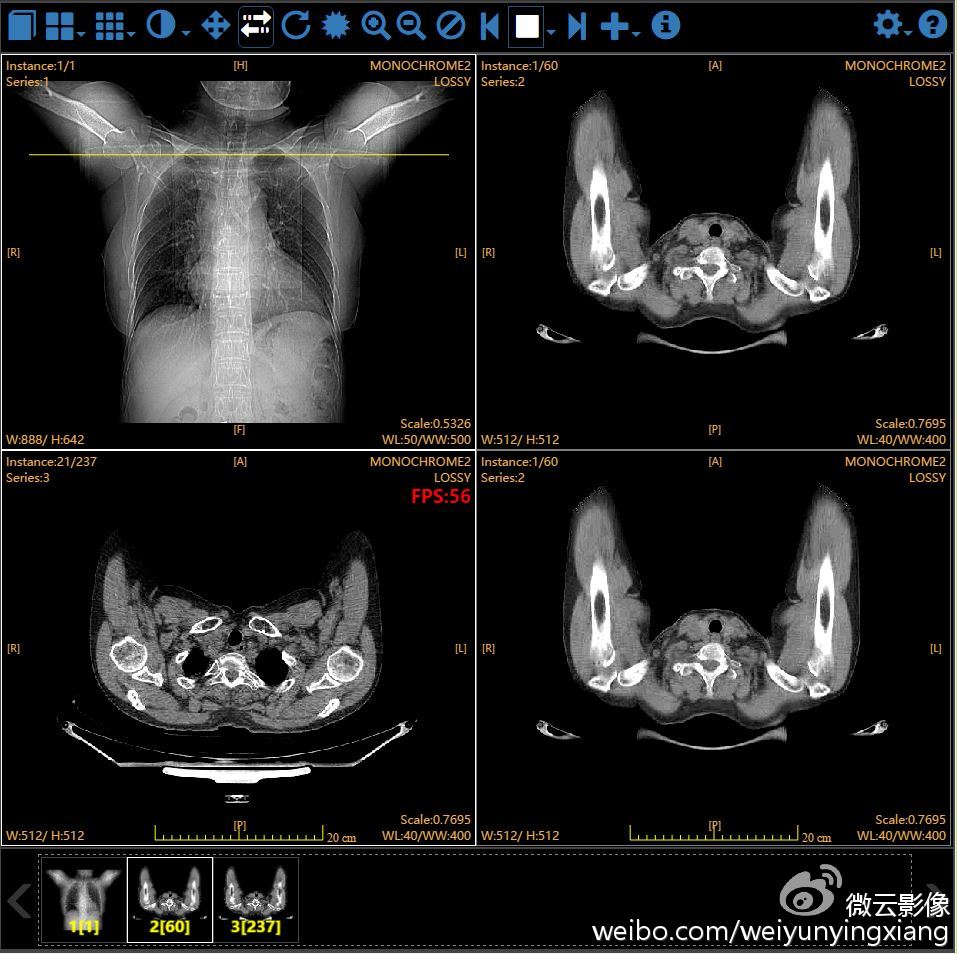

Sono stati acquisiti due esoscopi, strumenti che vanno a sostituire il più classico microscopio e che permettono di operare con speciali visori 3D: nel caso di tumori o di interventi di chirurgia spinale o funzionale, le immagini sono trasmesse in tempo reale su schermi di grandi dimensioni per l’ingrandimento di altissima qualità, senza perdere luminosità e dettaglio. A questi si aggiunge il sistema di imaging intraoperatorio multidimensionale 2D/3D, O-ARM: un sistema di imaging intraoperatorio che permette di compiere operazioni con estrema accuratezza ponendosi quale evoluzione dei precedenti sistemi Tac intra-operatori. Quest’ultimo viene utilizzato prevalentemente nei pazienti con disturbi del movimento e negli interventi di chirurgia spinale.

Nel contempo, le già presenti strumentazioni Surgical Theater, simulatori neurochirurgici e neuro-navigatori che rielaborano le sequenze di immagini bidimensionali acquisite durate gli esami diagnostici di risonanza magnetica (RMN) e di tomografia computerizzata (TC) costruendo modelli in 3D della parte anatomica interessata, sono stati aggiornati e arricchiti con software che consentono l’esecuzione degli interventi in realtà aumentata. Questa tecnologia è usata prevalentemente nella rimozione dei tumori cerebrali.